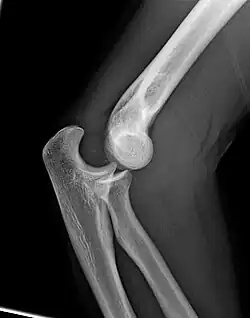

Right: AP X ray of a dislocated right elbow

The types of disease most commonly seen at the elbow are due to injury.

There are three bones at the elbow joint, and any combination of these bones may be involved in a fracture of the elbow. Patients who are able to fully extend their arm at the elbow are unlikely to have a fracture (98% certainty) and an X-ray is not required as long as an olecranon fracture is ruled out.[27] Acute fractures may not be easily visible on X-ray.[28]

Dislocation

Elbow dislocations constitute 10% to 25% of all injuries to the elbow. The elbow is one of the most commonly dislocated joints in the body, with an average annual incidence of acute dislocation of 6 per 100,000 persons.[30] Among injuries to the upper extremity, dislocation of the elbow is second only to a dislocated shoulder. A full dislocation of the elbow will require expert medical attention to re-align, and recovery can take approximately 6 weeks.